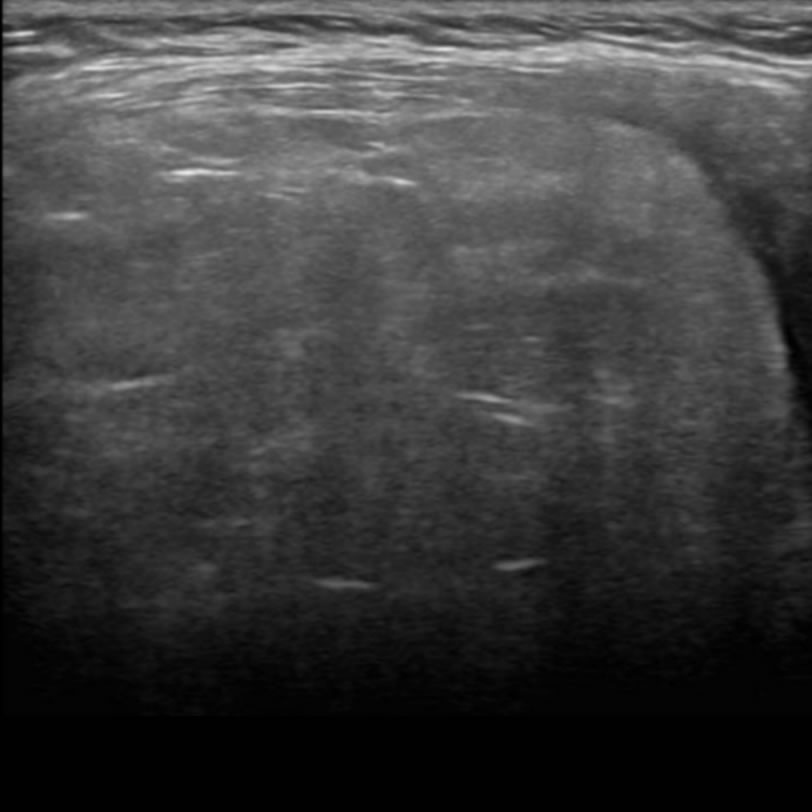

Masculino. 2 años. Tumoración axilar.